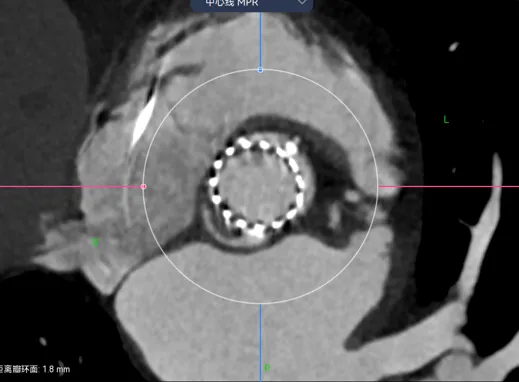

比如病例-6.可以看到瓣架比瓣环小了很多,这个时候虚拟瓣环是没有任何封堵作用的。

这个病例是一个明显的type0型二叶瓣挤压瓣膜,锚定区和封堵区都在瓣上,瓣上挤压瓣膜成椭圆导致瓣环位置跟着变椭圆。这时候如果想要没有瓣周漏,就一定要高放让封堵贴合瓣上限制的区域。Oversize是贴不到的。

再一个例子,病例-7,这个更明显了,可以看到虚拟的地方有一半的空隙。

这种病例你想要怎么实现良好的封堵呢?那一定是要在这个地方有覆膜区,而且可以完全贴上,一个层面一个层面看,可以发现找不到一个层面没有空隙的。

这个时候就要预估病人的术后瓣周漏风险了,需不需要一起放个封堵器,箭头指的地方都是导致PVL的地方。